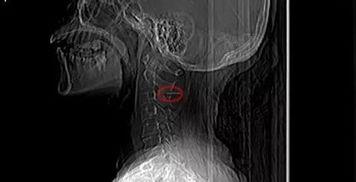

喉咙被鱼刺卡住最多见,。一般情况下,鱼刺、骨渣及果壳等异物最容易刺入的部位主要是扁桃体下端、舌根部等部位,枣核则容易卡在食道中。卡了异物,人的咽部会感到刺痛或有异物感,异物较大的话,吞咽也很困难。如果异物刺激喉黏膜,则会引起剧烈咳嗽,并因反射性喉痉挛及异物阻塞而出现呼吸困难,并可能有不同程度的喘鸣、失音、喉痛等。最严重的是,如果异物较大,而且嵌在声门上,则很快会造成窒息死亡。

遇到喉咙扎了鱼刺,可以先试着用汤匙或牙刷柄压住舌头的前半部,在亮光下仔细观察其舌根部、扁桃体及咽后壁,如果能找到鱼刺,可用镊子或筷子夹出。如上述方法不能奏效,或吞了流食后痛感加重、异物感更明显,应立即到医院看急诊。千万不要强行大口吞咽蔬菜、馒头,以为能把刺带下食道,这样只会使刺扎入较深的部位,或卡在食道内,造成更严重的后果。